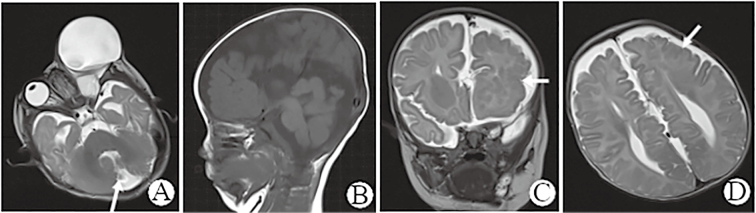

Clinical Observation on Orbital Teratoma of Delleman Syndrome Diagnosed by Fetal MRI Without Cutaneous Manifestations.